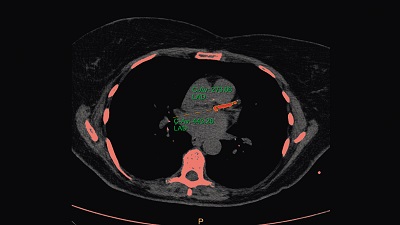

Calcium Score

One-click 3D calcium segmentation

One-click 3D segmentation and quantification for coronary arteries calcifications including mass, Agatston, and volume scores.

• Calcium scoring is achieved by performing automatic calculations on CT HU values in user-defined regions of interest.